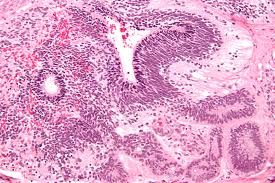

Teratoma refers to the usual tumors quite rare in nature. Discovering it a quite alarming process. You may wonder why. The reason is unlike the other tumors, it contains body parts. Shocked? The teratoma consists of hair, teeth, organs, and limbs. Around the world, many instances of rare tumor have shocked people. In general cases, tumors just consist of masses of the cell. The unusual reproduction of the cells can result in discomfort.

The tumor’s location is significant in deciding the kind of cells it may consist of. But, teratoma has cells that are found throughout the body. The cells replicate and result in the creation of the rare kind of tumor. So, the inclusion of different cells from the entire body is the reason you find brain cells, limbs, or even teeth in the rare tumors. Do you wish to know more? The, read ahead to get in-depth information about the tumor.

The word teratoma is a combination of two Greek words. While teras means monster and onkoma is synonymous with swelling. So, together it refers to monster swelling. The exact reason for the formation of the tumor is unknown. But, you need to understand that the tumor is the development of actual tissue development germ cell instead of the germ cells itself. So, the tumor consists of fully developed tissues. So, it contains bone, muscles, teeth, hair, etc. it can occur anywhere in the body, but is more common in females compared to males. But, newborn babies can also get tumors. The tumor usually found in newborns have a benign nature. It requires surgical intervention to alleviate the problem. The teratoma occurs mostly in the following body parts:

The teratomas are not cancerous. The benign tumors are surgically removed from the body. But, the problem is it can grow back even after the removal. The mature teratomas have diverse types. So, the further classification is:

• Cystic: The tumor enclosed in a sac contains its own fluid. It is also referred to as dermoid cysts.

• Solid: It is not self-enclosed. But, the tumor encompasses tissue.

• Mixed: As the name suggests, it contains both the cystic as well as solid parts.

Germ cells are one of the major causes of teratoma. The cells also are known as pluripotent can differentiate into other special cells. So, you can find it anywhere in your body. Most doctors agree that the teratomas occur due to the condition in primordial germ cells. The theory referred to as parthenogenic theory sheds light into the issue. The theory gives comprehensive information on the appearance of the hair, wax, and teeth with the tumor. Therefore, the teratoma has the appearance of a fetus (almost well-formed). The germ cells have a significant role in deciding the location of the teratomas.